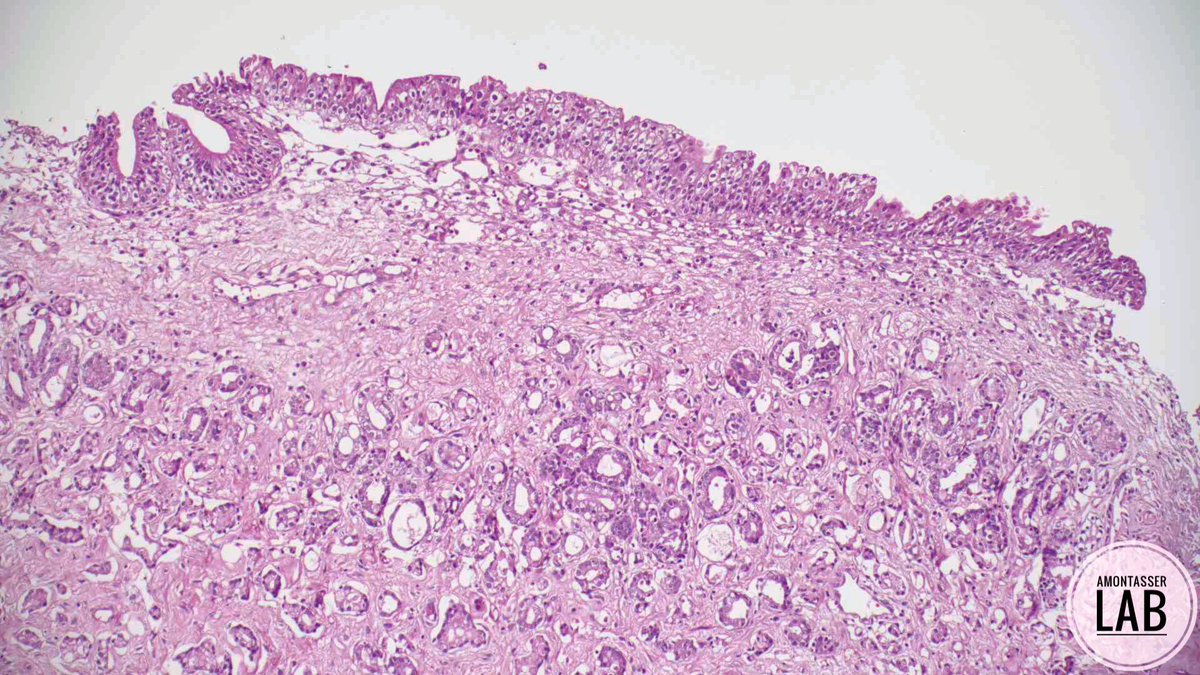

โ€ข Request form: M, 76 Y, prostate enlargement โžก๏ธ TURP โ€ข ๐Ÿ”ฌ: #GUpath #PathX #Pathology ๐Ÿคท๐Ÿปโ€โ™‚๏ธ